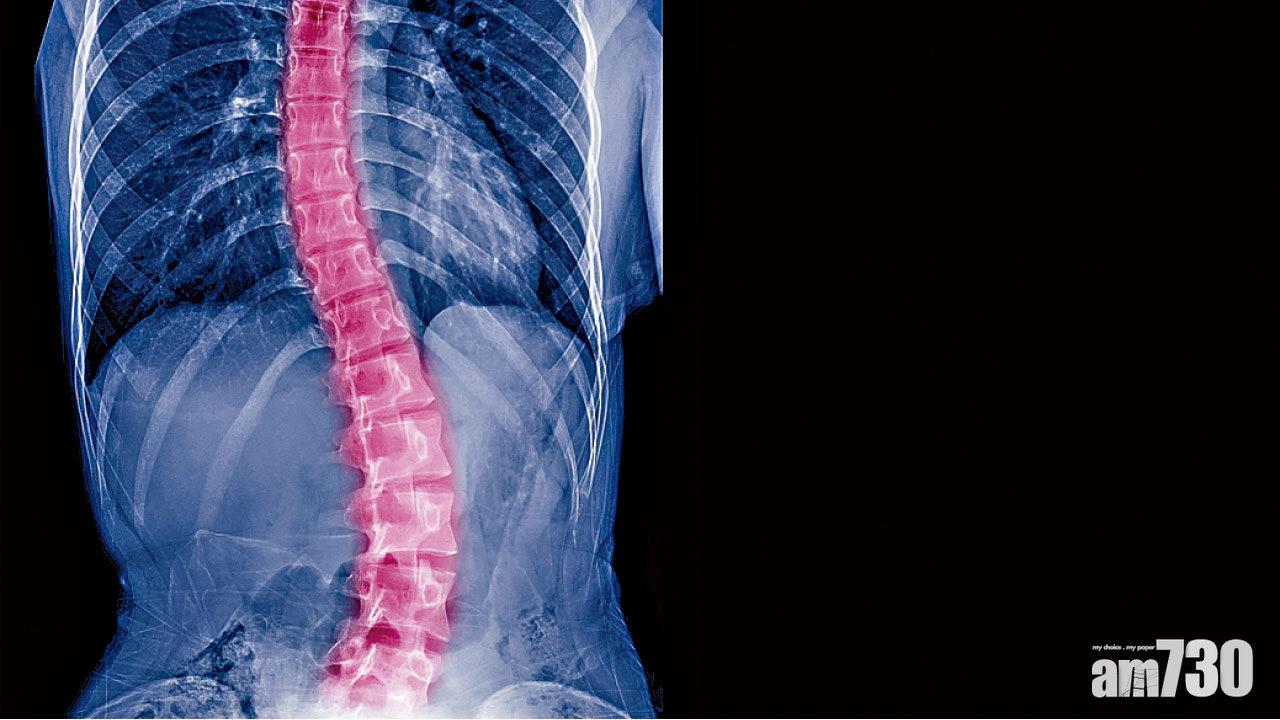

一般來說,脊柱側彎不是一個單純左右,或前後的側彎,往往合併旋轉畸形,形成一個三維畸形側彎。當拿到一張脊柱X光片,往往看到的是脊柱平面影像,不能準確反映病人的真實情況,手中的X光片只能起到參考作用,還需要結合臨床經驗,才能在治療中有的放矢,進行全面客觀的治療。